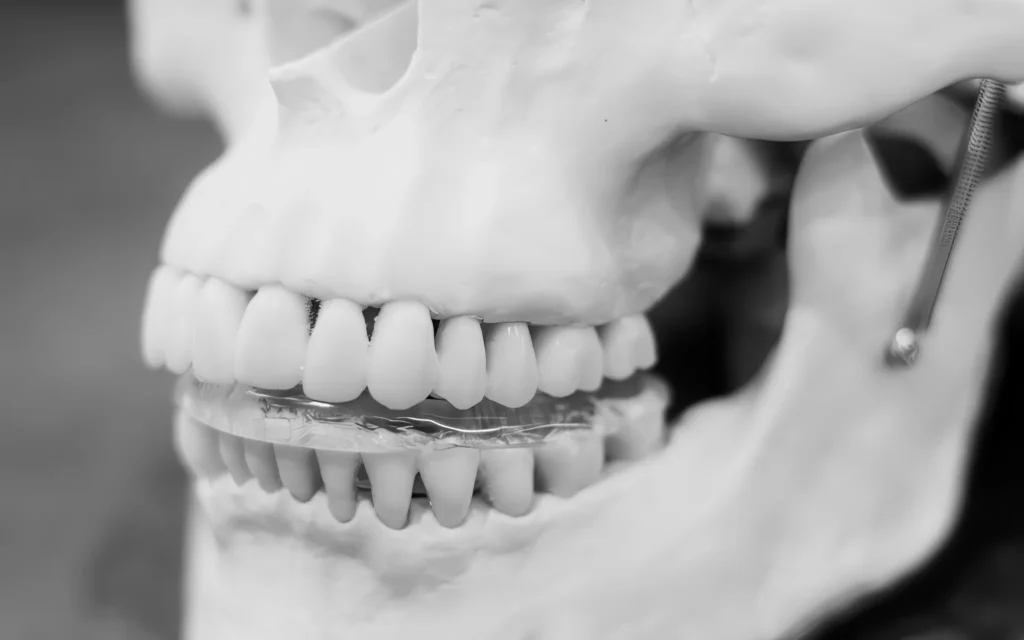

- Ночная жёсткая индивидуальная шина (фрезерованная/3D-печатная из биосовместимого полимера).

Шины: чем они отличаются (и зачем разные)

| Тип шины | Задача | Кому подходит | Примечание |

|---|---|---|---|

| Жёсткая окклюзионная | Разгрузка жевательных мышц, стабилизация контактов | Ночной бруксизм, мышечная боль | Индивидуально фрезерованная/печатная |

| Позиционирующая | Центрирует нижнюю челюсть | Смещения, щелчки | Носится курсами под контролем |

| Миорелаксационная | Снижает гипертонус | «Дневные стискиватели» | Лёгкая, чаще дневная |

| Диагностическая | «Примерка» новой высоты | План полной реабилитации | 2–6 недель |